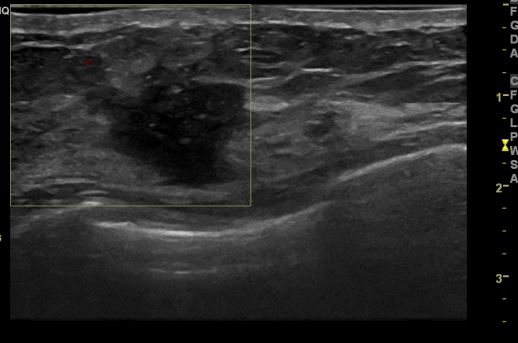

상기환자 간헐적인 유방의 통증으로 내원하신 50대 여성분으로 우측 3시 방향의 의심

스러운 멍울 조직검사 시행하여 우측 침윤성 유관암 진단 되었습니다.